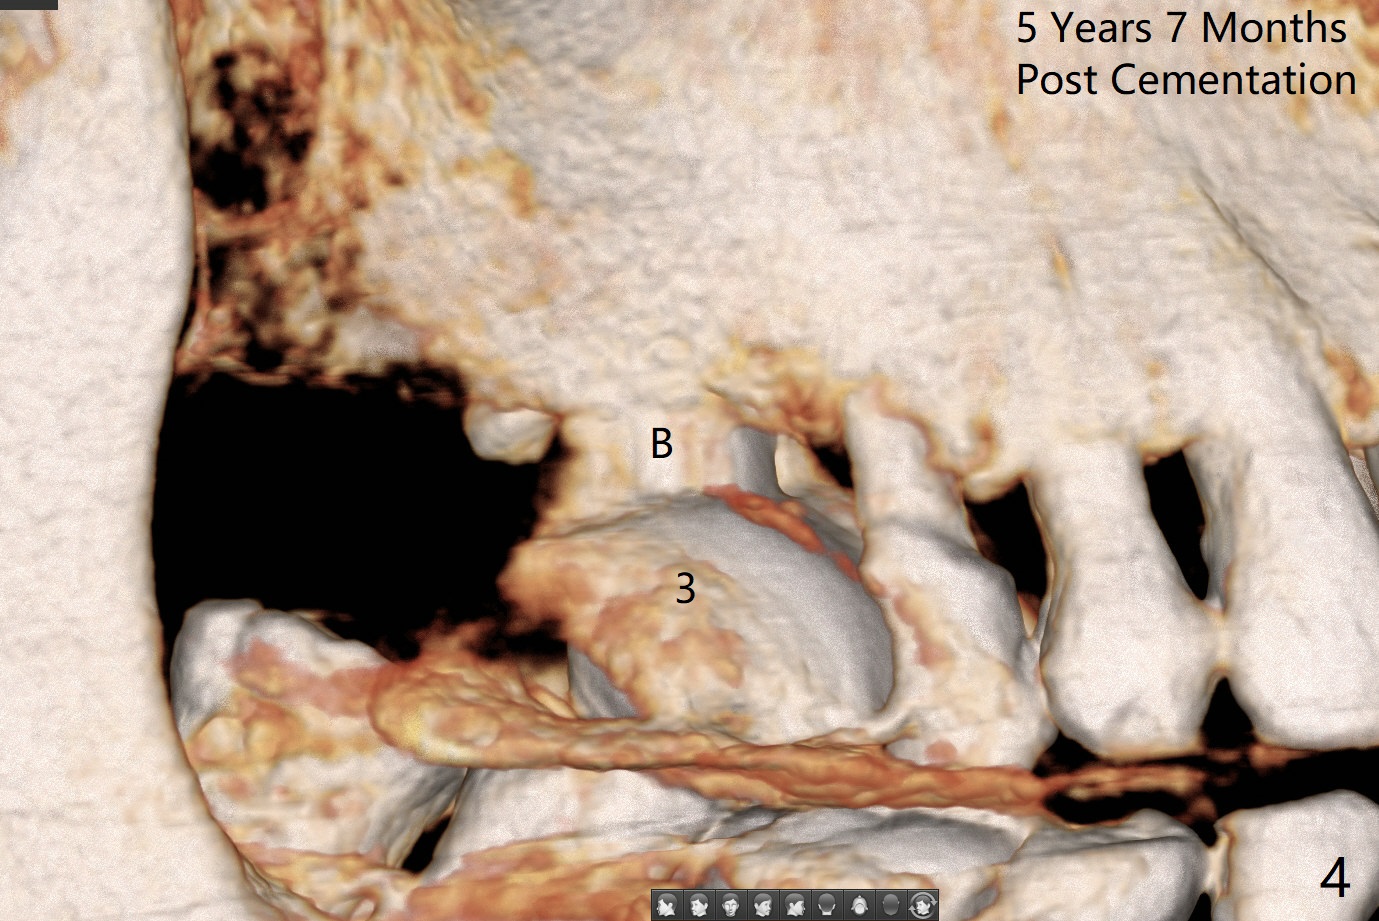

A 74-year-old woman returns for #19 implant consul-tation 5 years 7 months post cementa-tion at #3 (Fig.1). Since the implant at #3 (6x14 mm) has less ideal trajectory associated with free hand placement (Fig.3 (mild distolingual (L) thread exposure; Fig.1,4 (distal placemennt), guide will be fabricated for #19 implant placement. The lingual plate is thick and dense (Fig.2 L). To prevent drill and implant deviation buccally, a 5x11.5 mm implant will be placed as lingual as possible. A 5 mm cortical drill will be used before 2.2-4.5 mm ones being used for depth. The 4.0 mm drill will reach the final depth (apical underprep). A 17 mm long tissue-level implant will be placed. 17-5.5=11.5 mm (thread portion); 1.2 mm drill tip for the rough surface. Prepare 3.5x14 or 17 mm dummy implant to test the depth.